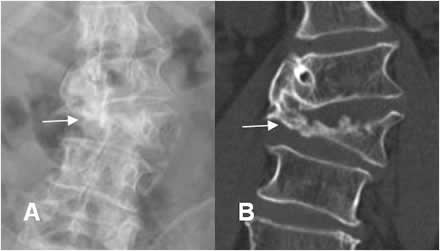

Fig 17. Hernia de disco.

A: Rx AP y B: TAC axial. Desviación lumbar derecha. Este hallazgo es secundario al espasmo muscular, ocasionado por una hernia paramediana.